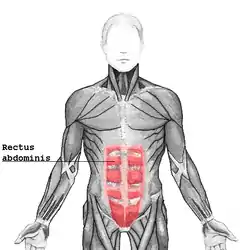

| Rectus abdominis muscle |